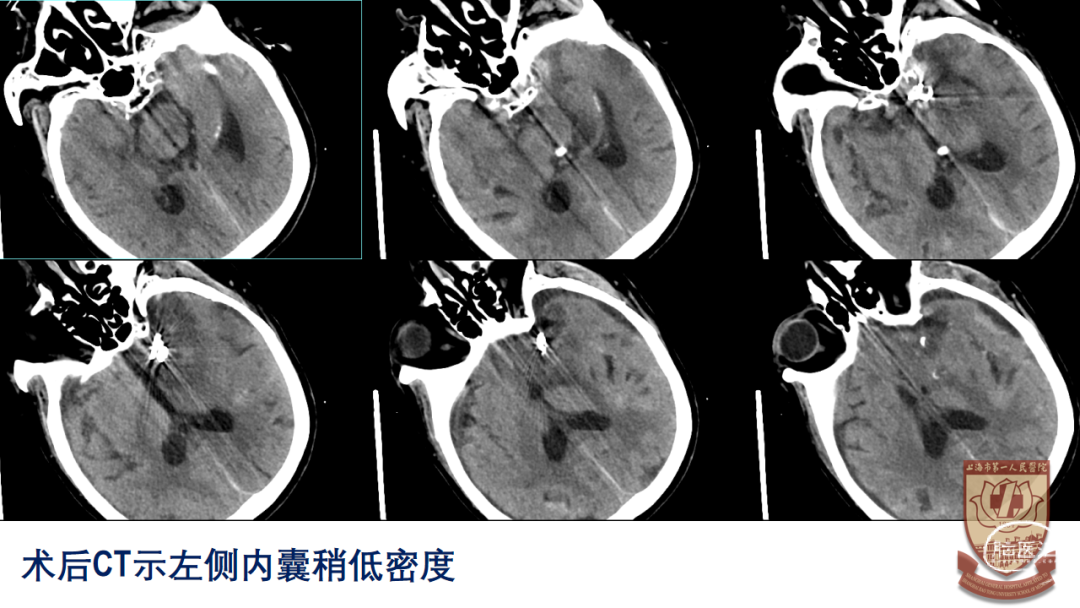

术后情况

GCS13-14分,左侧动眼神经麻痹,右侧肢体肌力IV-

转康复医院治疗